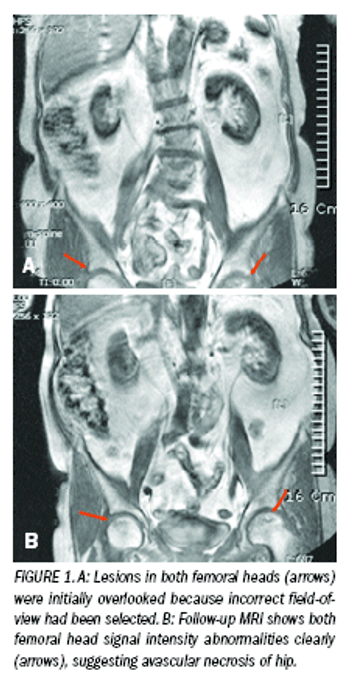

Critical hip disorders show upon spinal imaging studiesByHyung Seok Kim, MDJuly 1st 2009When patients are suffering from back pain and radiating pain in their lower extremities, it is usual to suspect that the symptoms are caused by a spinal disorder.